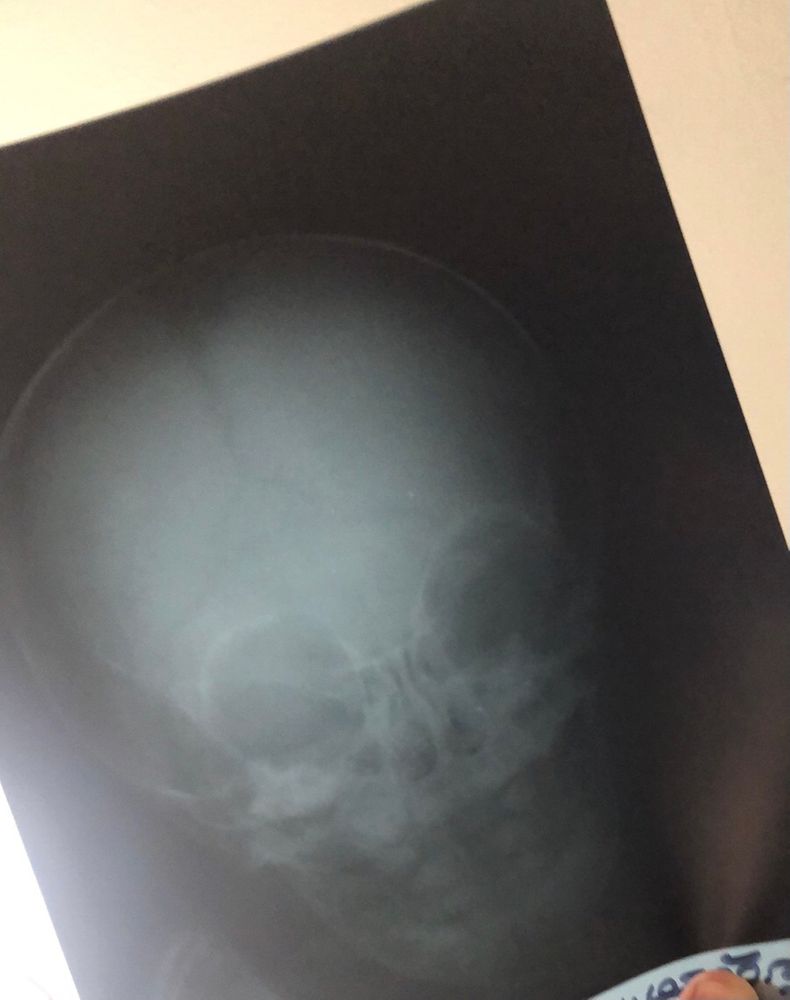

На рентгене головы, видно зубки, но пока что из нету

Девочки, нам 7 месяцев, зубов нету. Предпосылки есть, но пока что ничего не виднеется. Дело в том, что мы недавно упали с дивана, я испугалась, скорая-Больница-рентген и все прилагающие. Так вот, на рентгене видны ЗУБЫ, 4 штуки, 2 клыка, и снизу 2 зубика под клыками. НО... пока что зубов нету. Вот если на рентгене видно зубы, может они там вот вот полезут? Или это значит - что они полезут, но в своё время после всех. Просто они там будто уже на выходе. Ничего не понимаю.